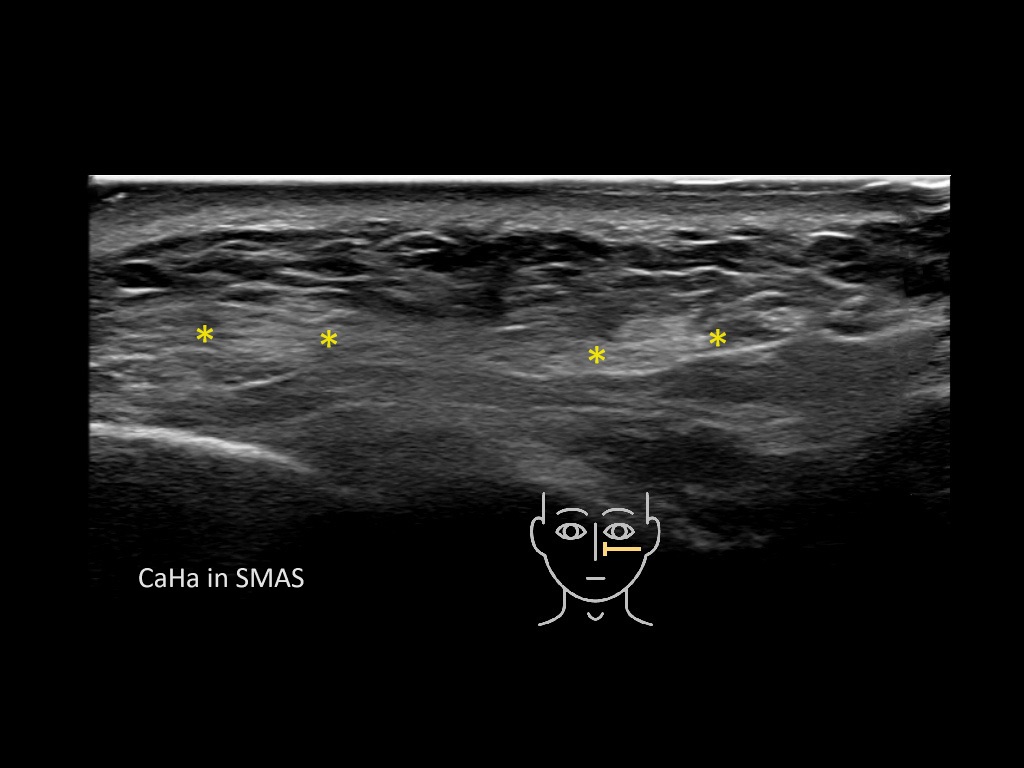

Filler deposits may end up unintentionally in the SMAS or fascial layers of the skin. Very often this will not lead to adverse events, however, adverse events ( nodules, migration / redistribution impaired muscle movement and smiling and malar edema) are are often related to filler ending up in the SMAS or fascia.

Study the first image to recognize the different layers. If you are sure about the layers, swipe to the second image to view the answer (if applicable).